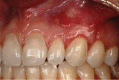

Gingival recession is an oral health problem that affects a large part of the population. Several treatments are suggested in the current literature; among them is the use of buccal fat pad grafting. The objective of this case report is to describe the treatment of a Miller Class I gingival recession using a nonpedicled buccal fat pad graft immediately after performing the surgery for buccal fat pad removal (bichectomy technique). First, bilateral surgical removal of the buccal fat pad was performed with the main objective of eliminating oral mucosa biting. The recipient site was prepared to receive a portion of the fat pad that was cut and macerated in a size that was sufficient to cover the recession. The patient was followed up at 15, 30, 60, and 365 days postsurgery, and the results showed an elimination of the oral mucosa biting and complete coverage of the gingival recession. It was concluded that the nonpedicled buccal fat pad graft is another option for the treatment of Miller Class I recessions.